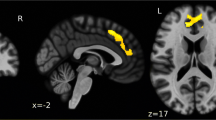

Dynamic brain activation during fear responses to UCSs is illustrated in Fig. 2 (healthy control #2 provided as an example). The visual lightning symbol elicited visual cortical activity that peaked at approximately 80 ms and subsequent activation of the inferior and lateral temporal and posterior parietal areas that peaked at 80–150 ms. In addition, fear conditioning activated the bilateral insula and amygdala, which peaked at 150–200 ms. Notably, no discernible activation was observed from the ACC.

Dynamic brain activation of fear responses in one participant (healthy control #2). Brain activation at − 300 to 500 ms was mapped onto the individual’s MRI images (two axial views and one sagittal view) to observe cortical and subcortical neural responses to pain-related fear. In response to UCSs, cortical activity peaked in the visual cortex at approximately 80 ms, followed by clear activation in the inferior and lateral temporal and posterior parietal areas at 80–150 ms. Subsequently, activation of the bilateral insula and amygdala peaked at 150–200 ms and ended at 200–250 ms. No clear activation was observed over the ACC in the corresponding time interval. The amplitudes of underlying neural activity were converted to z scores and color coded